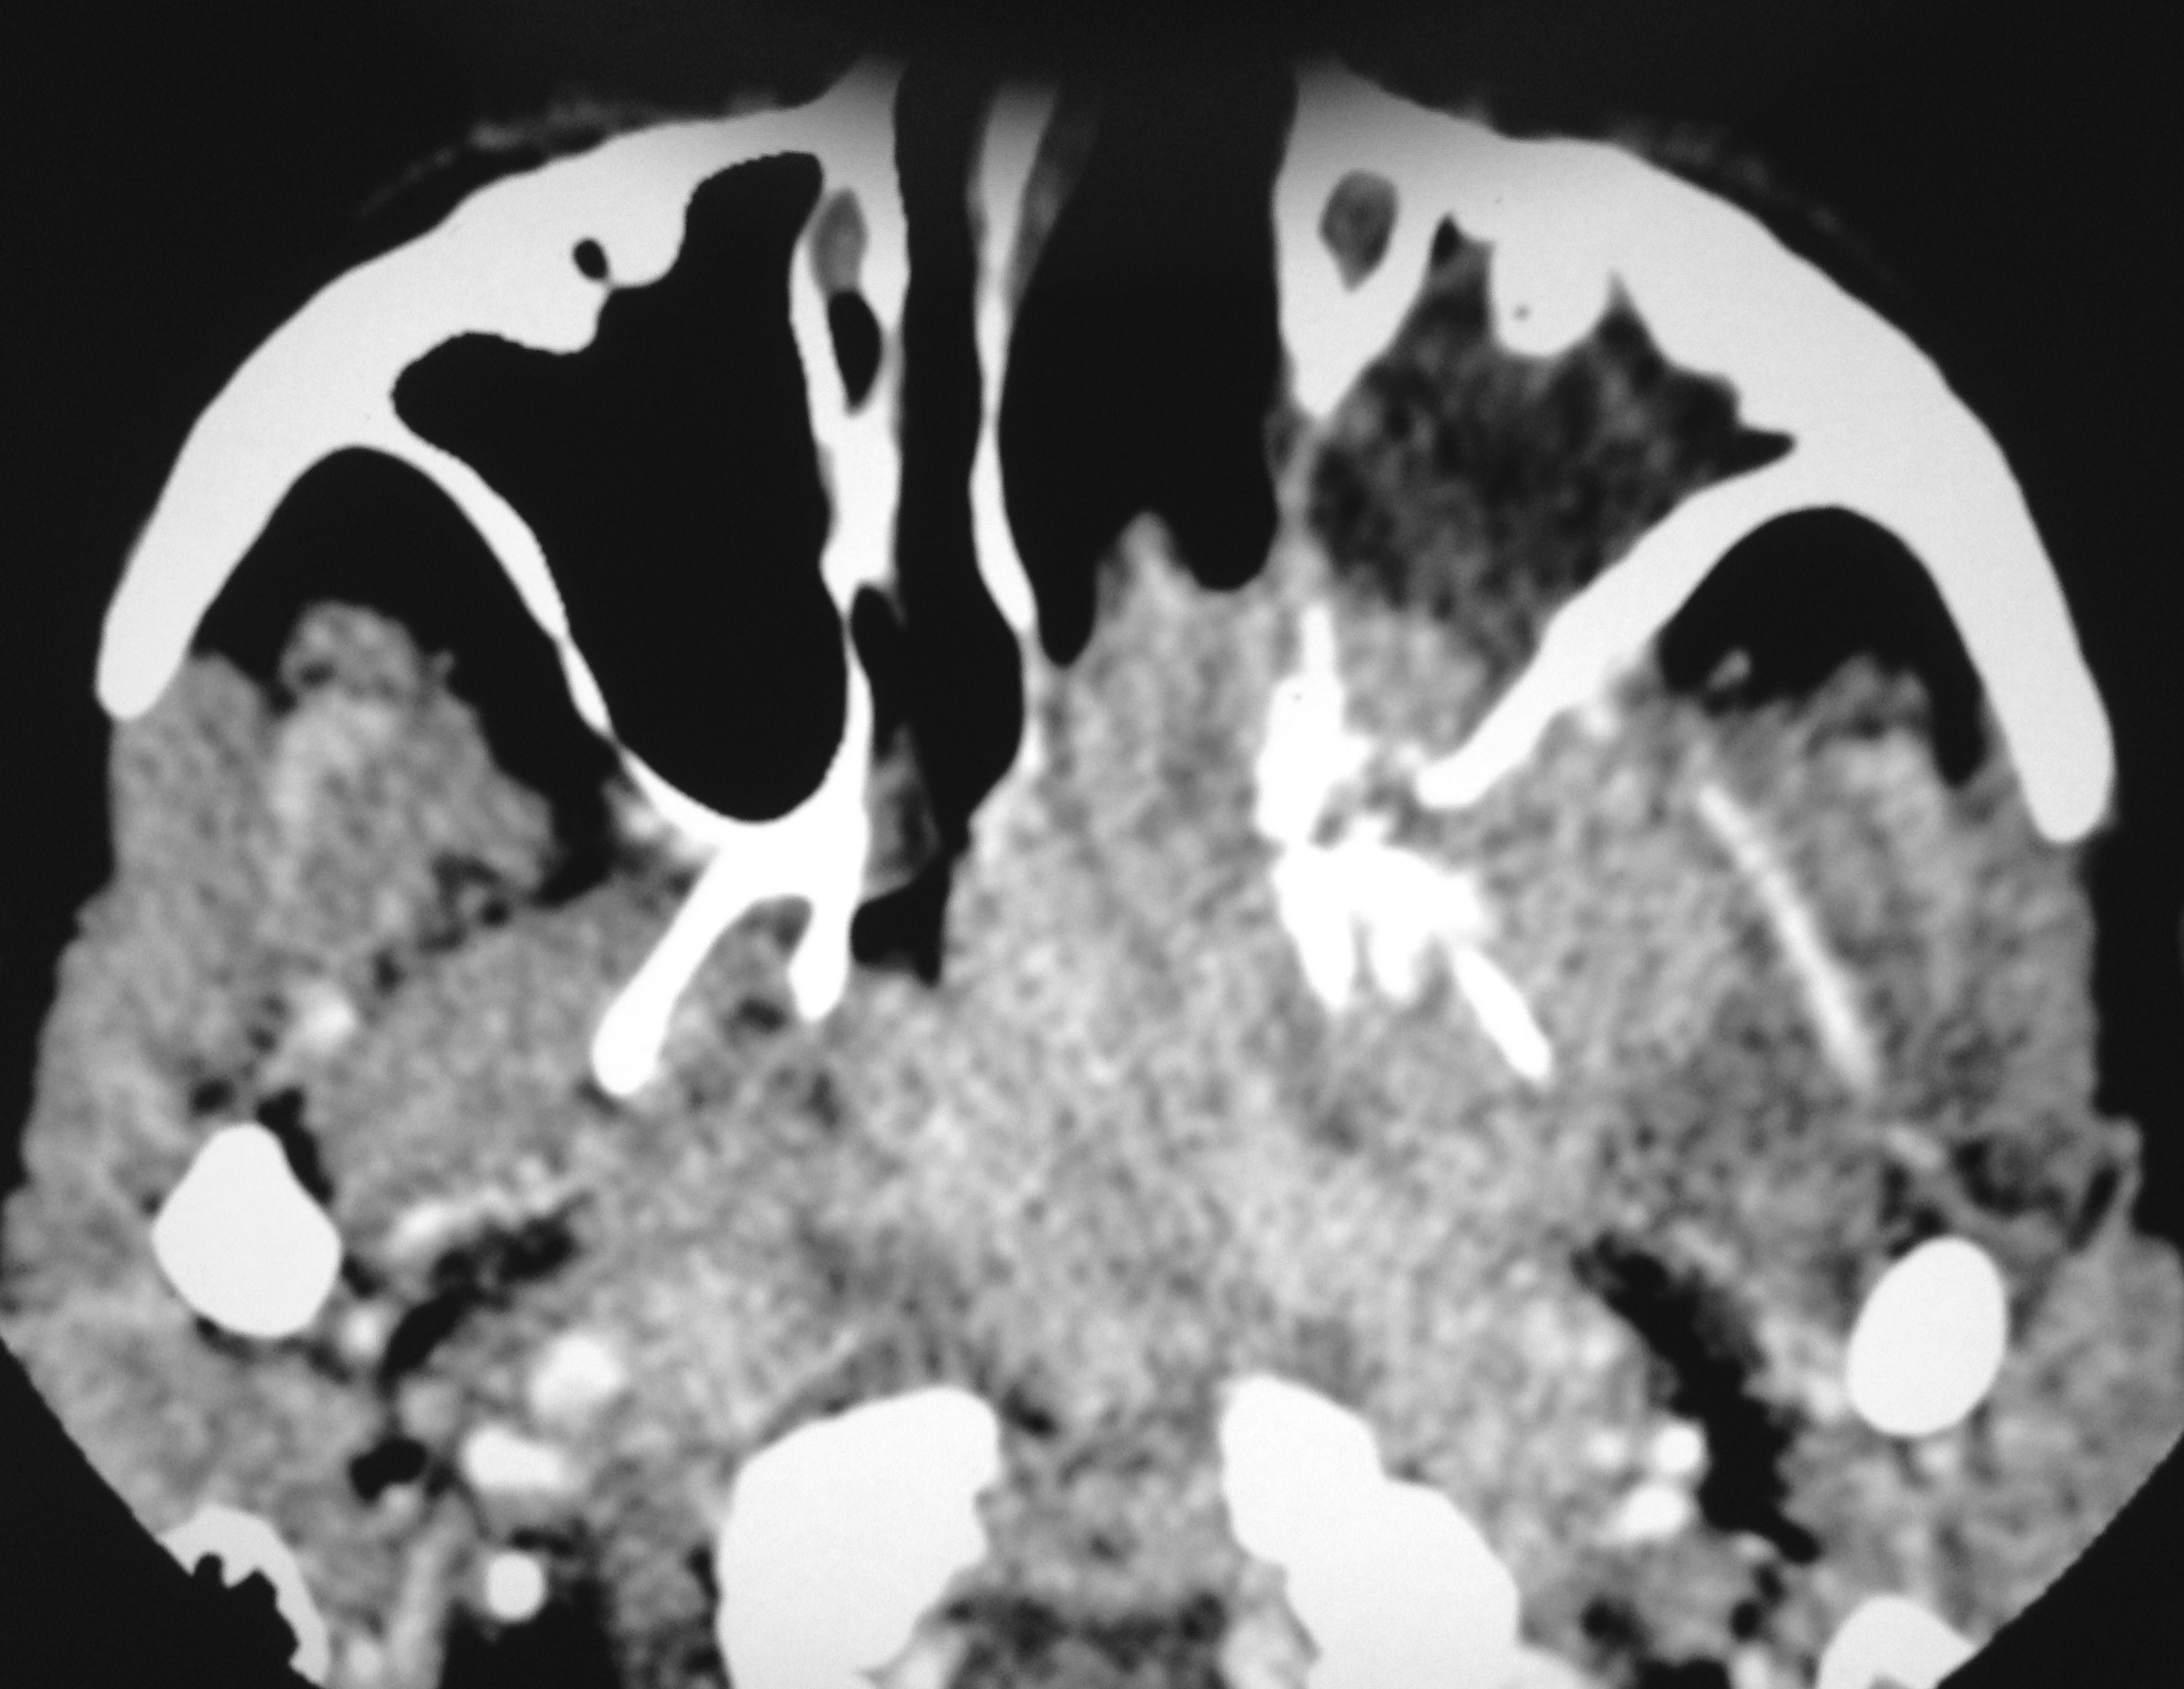

Nasopharyngeal carcinoma, Orbital apex, Cavernous sinus, CT scan

Nasopharyngeal carcinoma is a malignant disease and is more common in males than in females with M:F ratio of 3:1. It has a bimodal peak at 16-20 and 46-50 years of age. Orbital involvement is seen in 3.2% and bilateral orbital invasion occurs in 0.7% of patients with nasopharyngeal carcinoma. Imaging has significant role in detecting the early nasopharyngeal carcinoma, tumor staging, involvement of lymph node, monitoring the patients after the therapy, to detect recurrence and radiation associated changes in the soft tissue and bone. We report a case of aggressive nasopharyngeal carcinoma in 22 years old male who presented with rapidly progressive diminution of vision.